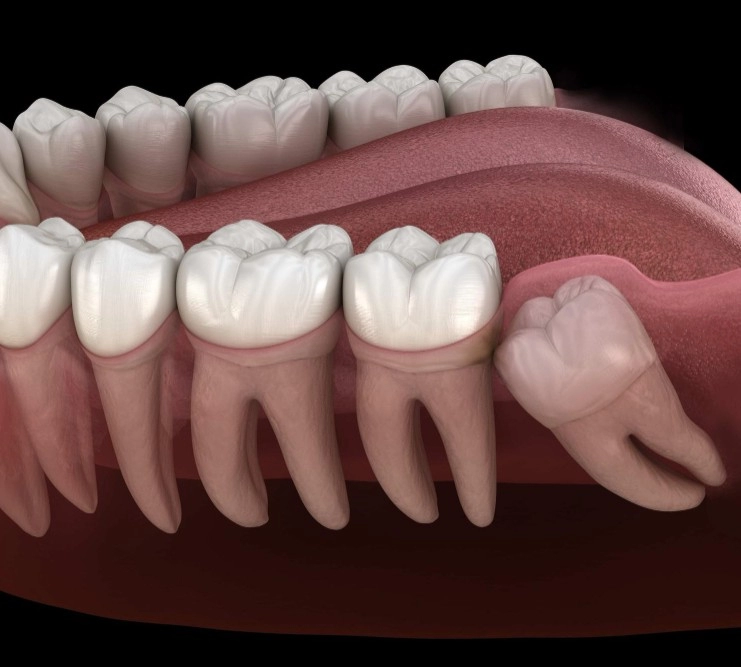

Боль, связанная с зубом мудрости, является распространенной проблемой, с которой сталкиваются многие пациенты. Зубы мудрости, или третьи моляры, обычно прорезаются в возрасте от 17 до 25 лет, но могут начинать прорезываться и гораздо позже. Этот процесс может сопровождаться болью в десне, отеком, болью в горле, повышением температуры тела. В таких ситуациях у многих возникает вопрос, что делать, если болит зуб мудрости, и как справиться с этой проблемой на разных этапах.

Болезненность зуба мудрости может быть вызвана различными причинами. Понимание этих причин помогает определить, что делать, если болит зуб мудрости, и как правильно действовать.

Определение причины боли в области зуба мудрости важно для выбора правильного способа её устранения и предотвращения осложнений.